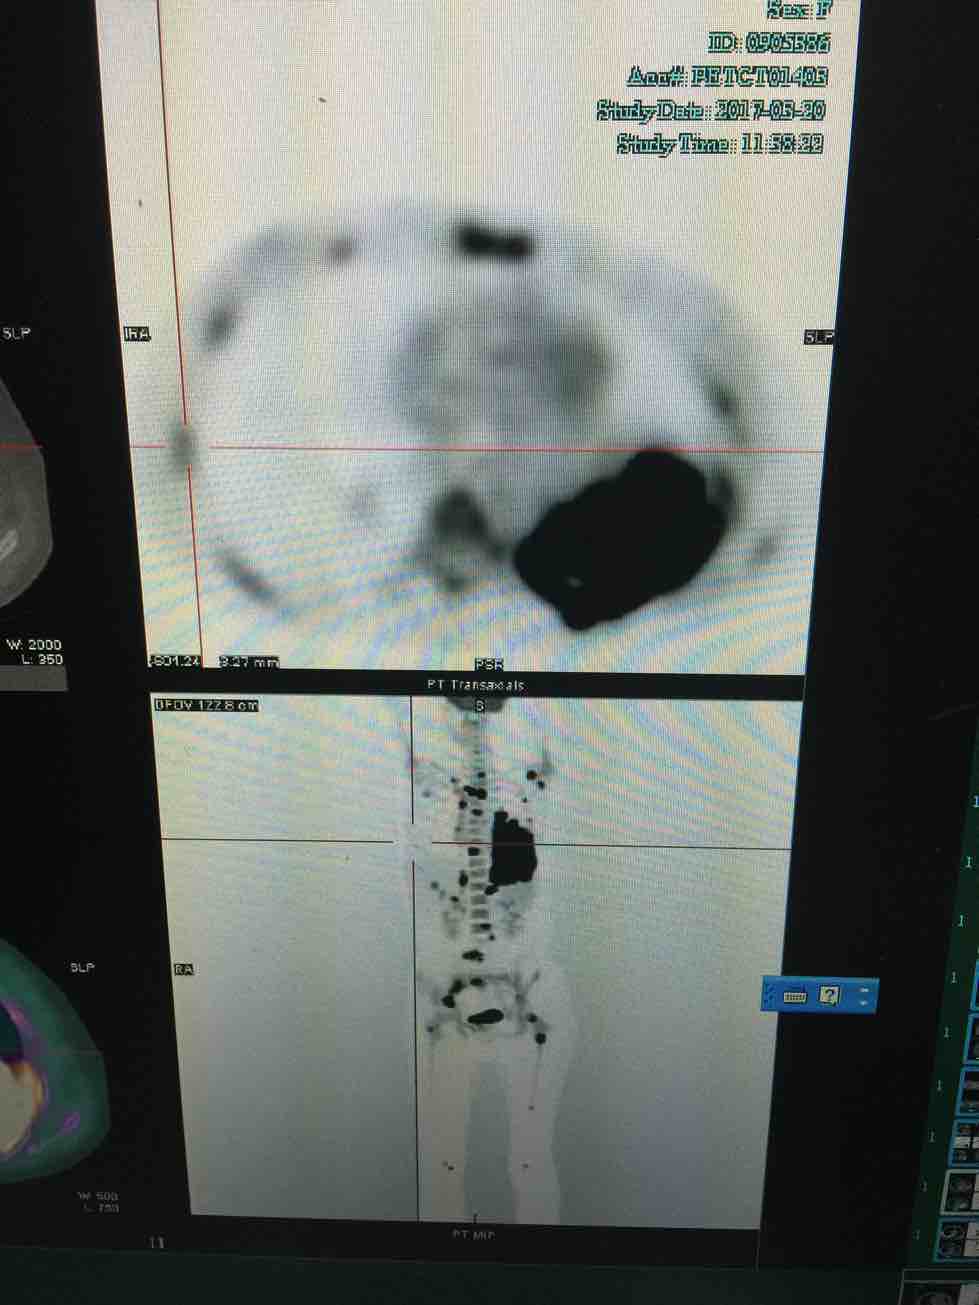

最近妈妈肺癌晚期,pe-ct进展很快,肺部肿瘤都有8公分多了,各处转移,包括脑转,身体也不太好,因为伴有阻塞性肺炎,每天晚上高烧39度,退烧药效果好,化疗不敢上,基因又是全阴,凯美纳也试了,无效,医生建议上阿帕替尼又叫艾坦,同时肺部低剂量放疗,这个方案可行吗?

片子上的黑点是转移吗